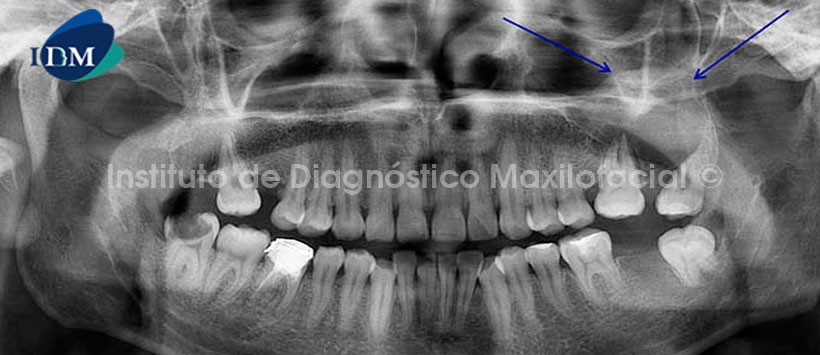

A la radiografía panorámica (Fig.1) se observa la presencia de una imagen radiopaca de densidad de tejido blando proyectada sobre el proceso alveolar del maxilar superior izquierdo y la apófisis cigomática, comprometiendo la pared basal del seno maxilar, así como la reabsorción ósea a nivel del tercio apical de la pieza 2.6 y se extiende hacia el proceso alveolar correspondiente a las piezas 2.7 y 2.8; produciendo la divergencia radicular de esta última.

También se observa la ausencia de las piezas 1.6, 1.8 y 3.7;  la pieza 4.6 con restauración coronaria con falta de sellado,  obturación parcial de conductos y ensanchamiento del espacio para el ligamento periodontal a nivel apical con aumento de la densidad ósea circundante sugerente de osteítis condensante; además de la pieza 3.8 con orientación bucolingual e impactada sobre el borde anterior de la rama ascendente, con una   imagen radiolúcida por distal de la corona, a descartar pericoronaritis; y la pieza 4.8 con una lesión cariosa amplia y profunda con probable compromiso pulpar.